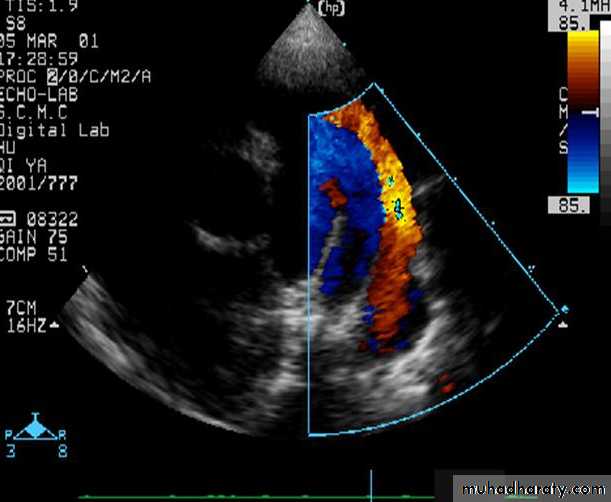

PATENT DUCTUS ARTERIOSUS (cont.)

Echo: is diagnostic2D echocardiogram can idendtify the PDA which can be confirmed by Doppler.